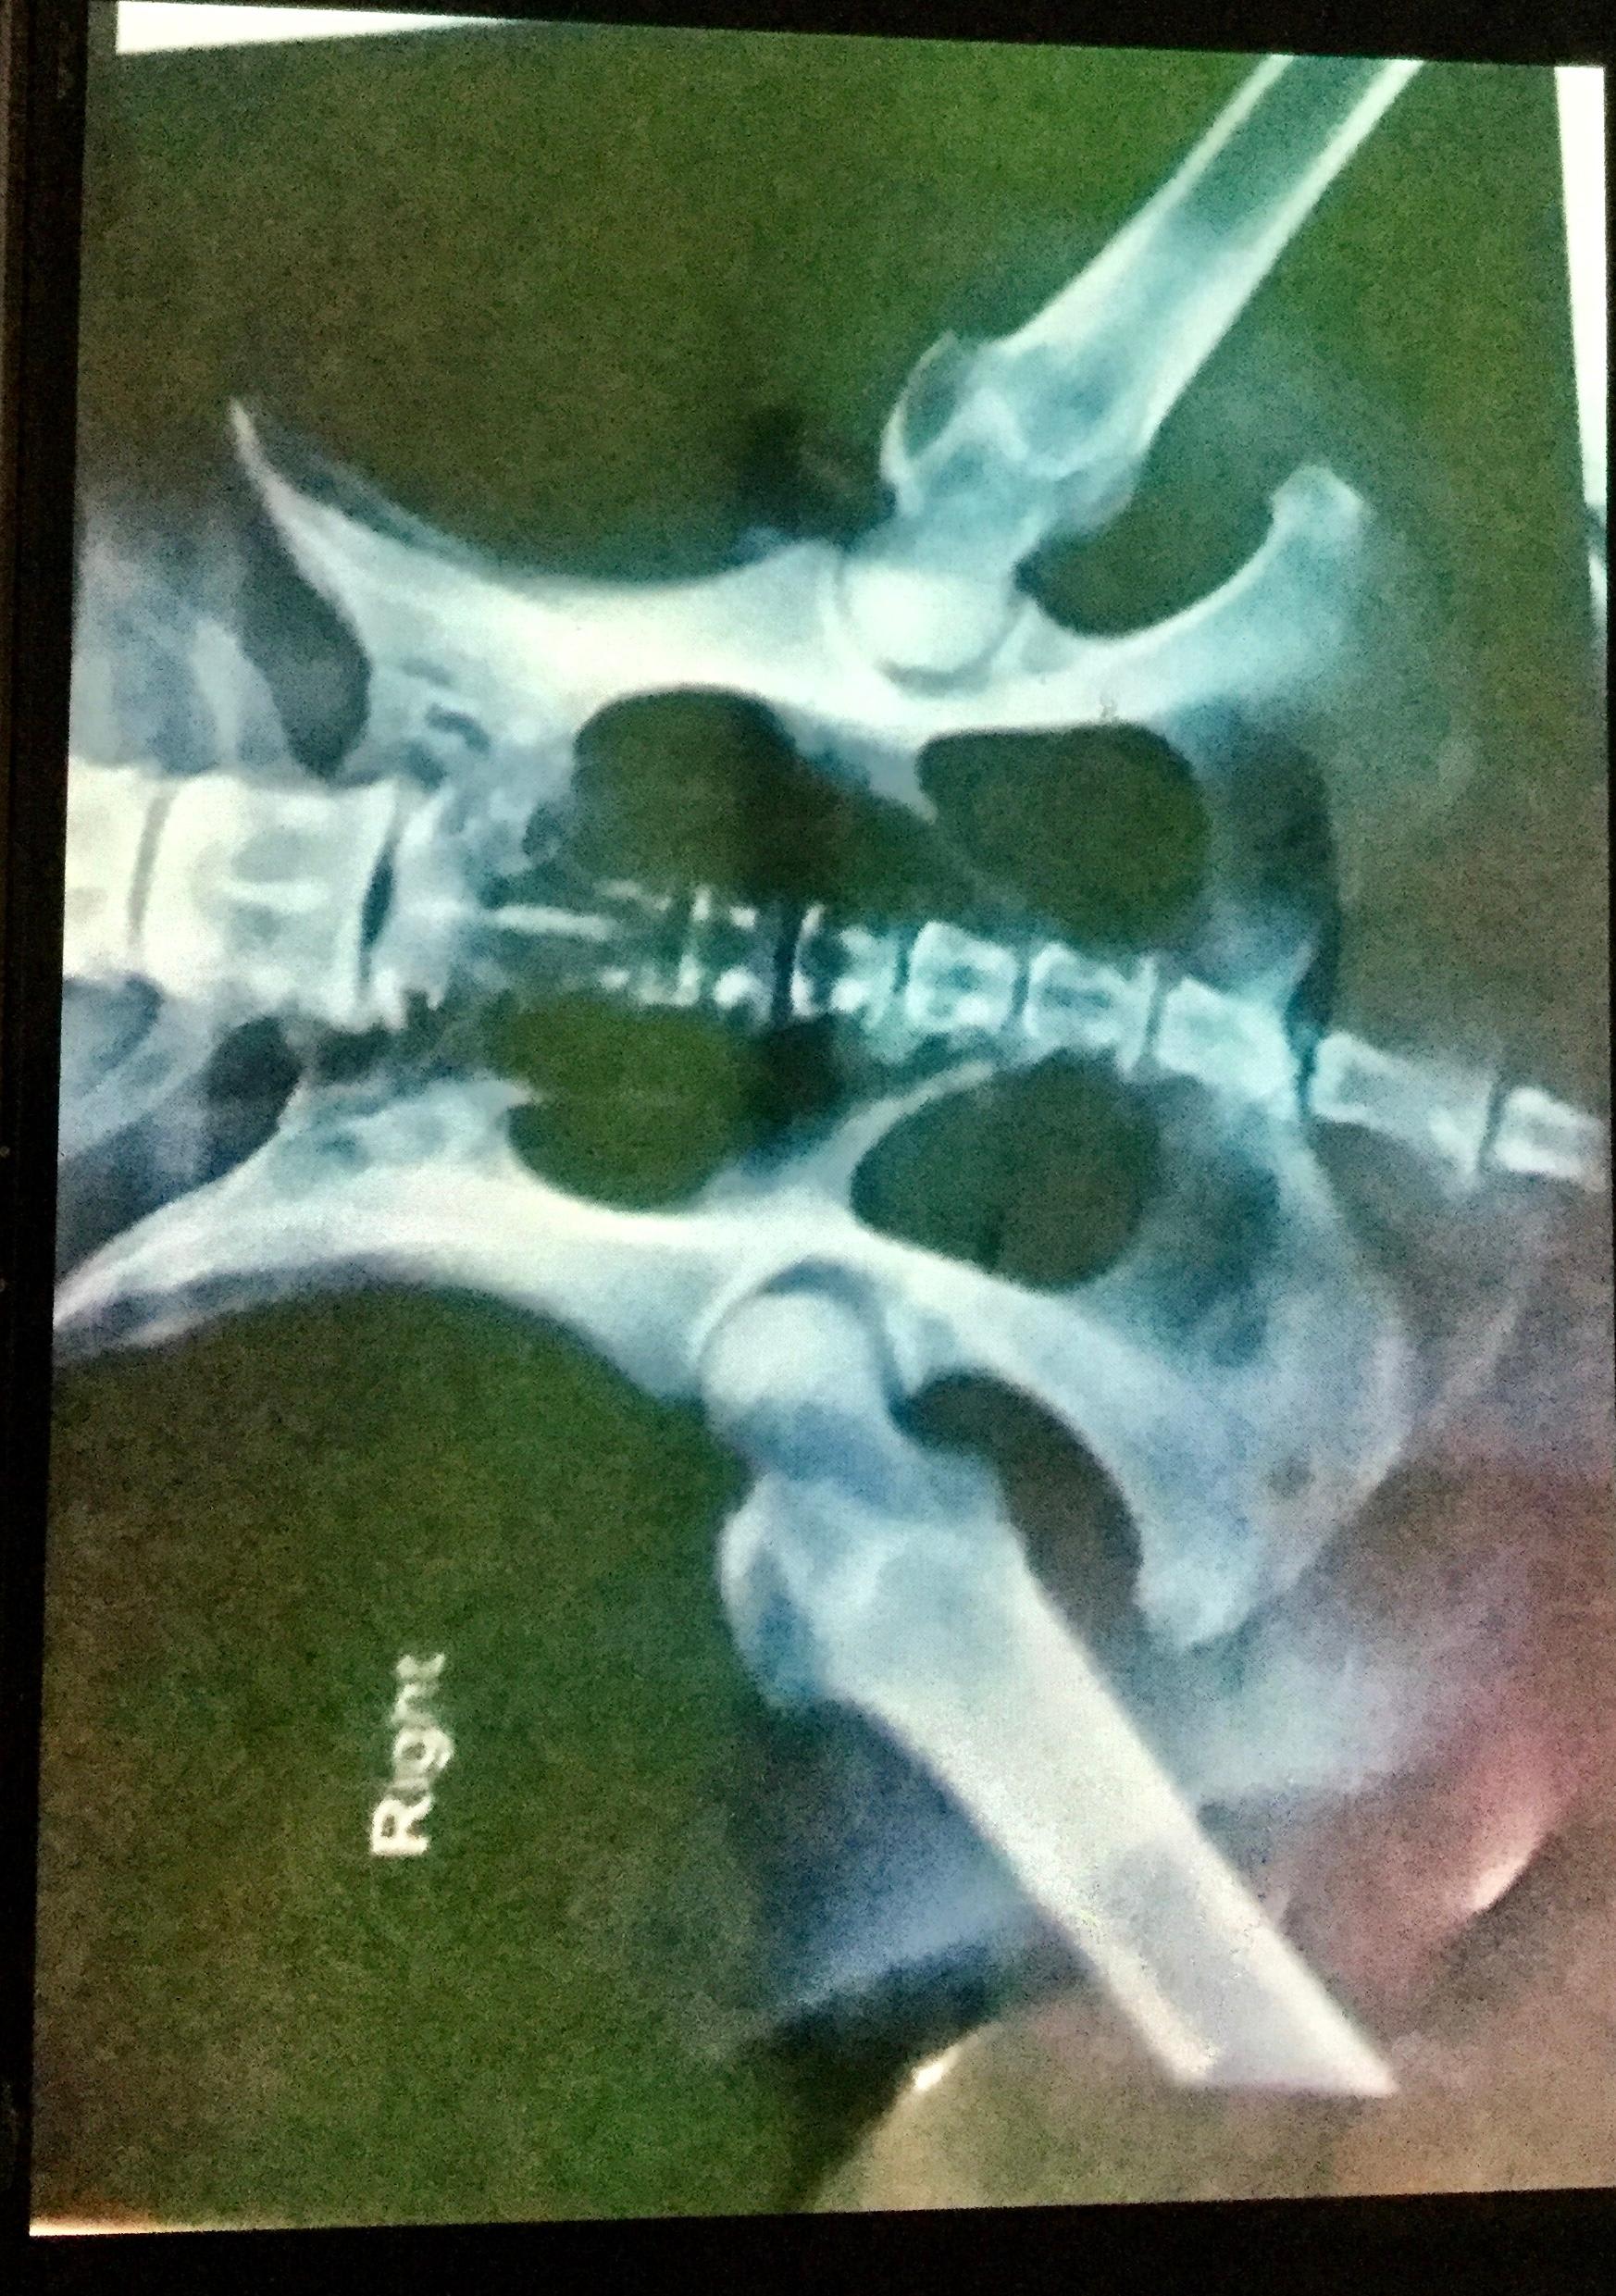

female Lab 10. Cannot put her hind left leg down. Since past 7 yrs it’s getting worse. Earlier she was active . The vet did physical examination and these xrays but have not come to a conclusion if it’s hip dysplasia, muscle myopathy or arthritis. Initially we put her on Dasuquin with MSM to which she responded . At present we are giving her Beaphar HD and Kalk tabs. Also Condrovet Force HA, Nurokind-Pet and Digene antacid. I want diagnosis and what treatment to be given . Please help. Desperate

Hello. The hips do look pretty good. I would ask your veterinarian to examine & determine if it is possible that Zoi has injured her knee. I would be especially interested in your vet conducting an exam looking for a cranial drawer sign that would indicate an anterior cruciate ligament tear, a common injury in larger breed dogs. Hope you find an answer to Zoi's pain & discomfort & thanks for using Petco Pet Education Center, formerly Petcoach.